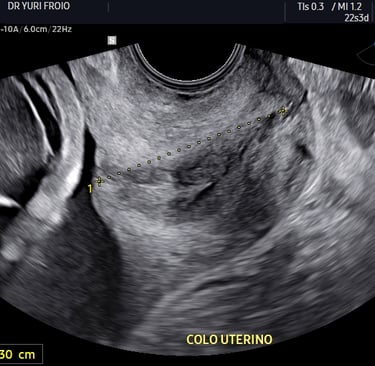

Esse exame é geralmente realizado entre 20 e 24 semanas de gestação. Ele tem como principal objetivo avaliar a formação do bebê, identificando possíveis malformações, além de observar o crescimento fetal e a placenta. No entanto, outro ponto muito importante e, às vezes, pouco comentado, é a avaliação do colo uterino, que pode ajudar a prever e até evitar o parto prematuro.

Durante o ultrassom, avaliamos o comprimento do colo do útero por via transvaginal. Um colo curto — geralmente considerado menor que 25 mm — pode indicar maior risco de parto prematuro. Essa medição é simples, rápida e indolor, e pode fazer toda a diferença no acompanhamento da gestação.